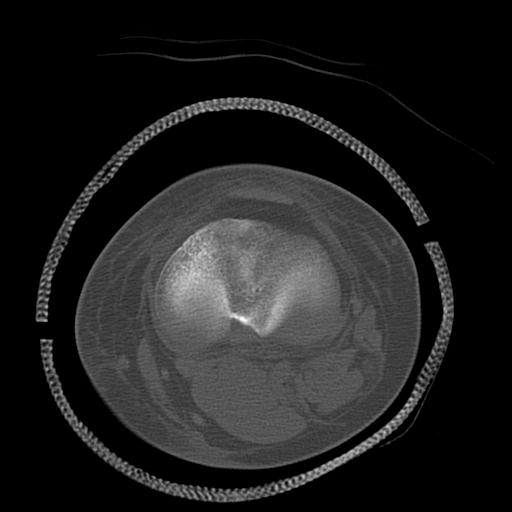

49554 3/13 膝 4R 3/16 4R 1/18 2R 78歳男性 膝蓋骨骨折